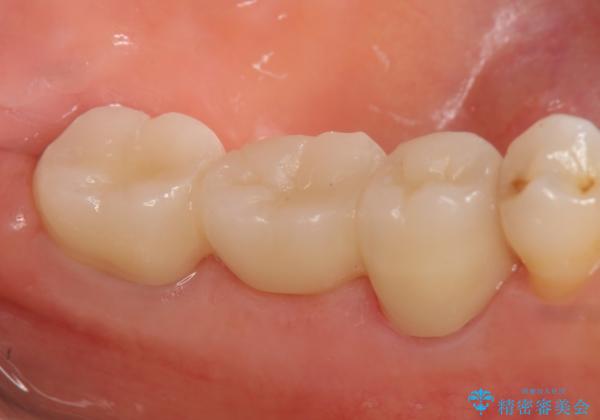

骨の定着を待ちポケットが3mm(正常範囲内)であることを確認後、オールセラミッククラウンによる欠損補綴を行いました。

今回用いたオールセラミッククラウンはジルコニアフレームという白い素材の上にセラミックを盛っているため、審美性が非常に高いのが特徴です。

また、ジルコニアは人工ダイヤモンドの材料にも使われているほど高い強度を持っており、そのためオールセラミッククラウンは審美性だけでなく、奥歯やブリッジの補綴も可能とするクラウンです。